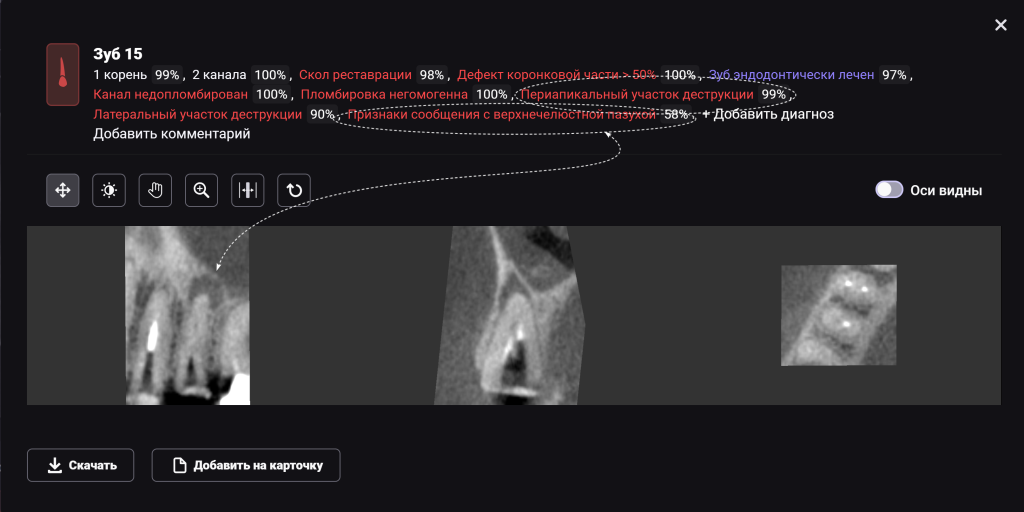

Для принятия клинического решения врач проанализировал данные осмотра и рентгенологического отчета Diagnocat. В отчете содержится оценка ранее проведенного лечения и данные о наличие признаков периапикальных изменений

Обратите внимание на высокий процент вероятности, который предлагает Diagnocat. Принято решение о сохранении зубов и проведении повторного эндодонтического лечения